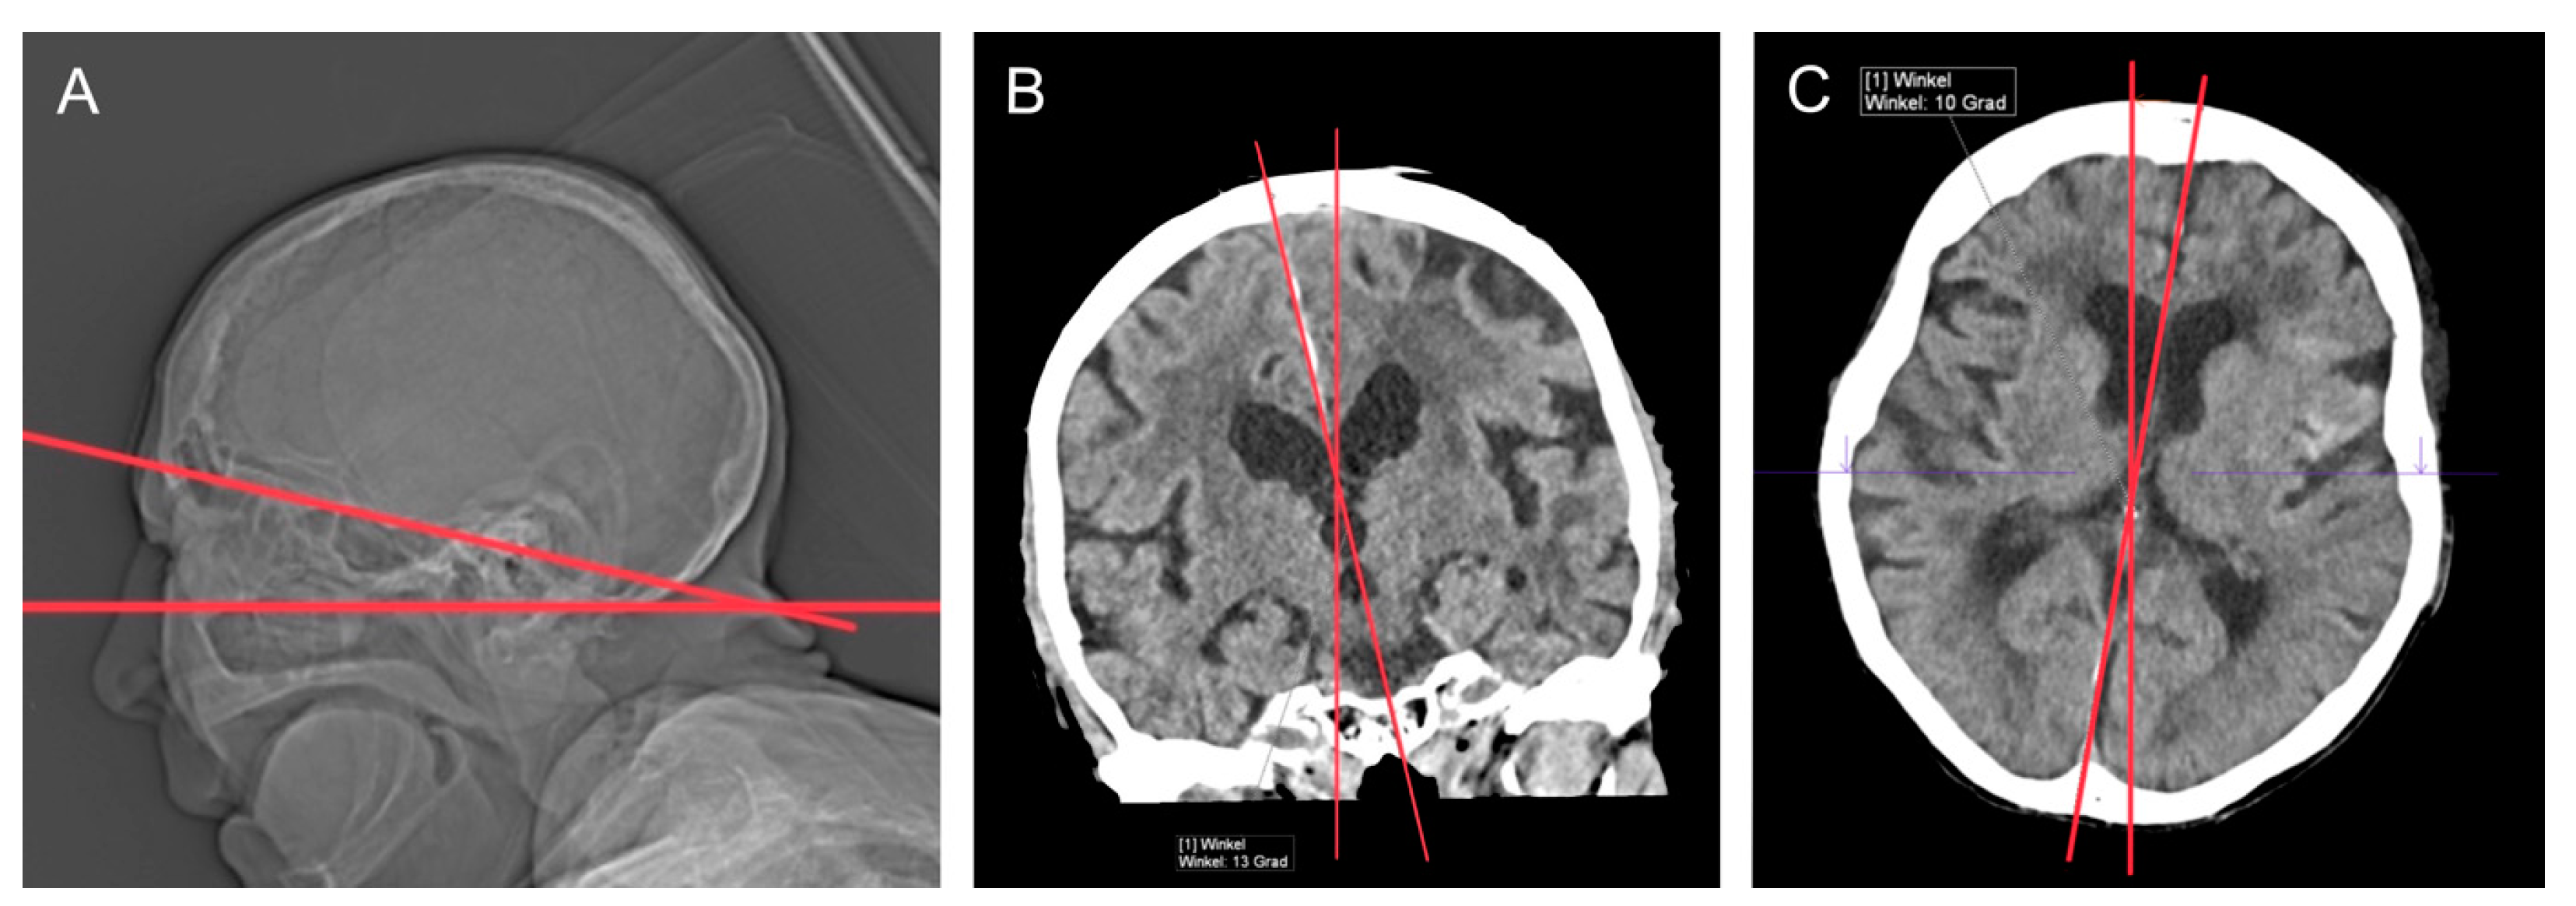

2.2. CT Technique

3.3. Clinical Reports